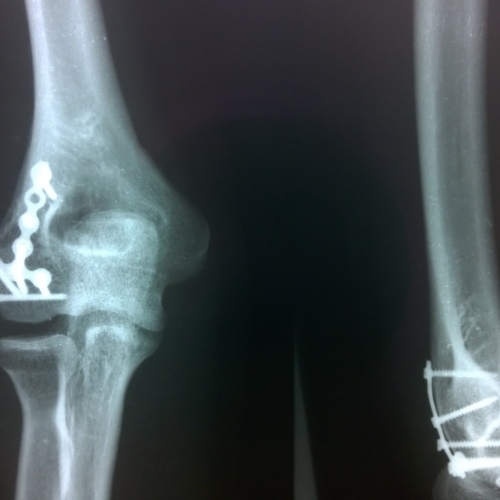

Закрытый перелом мыщелка плечевой кости